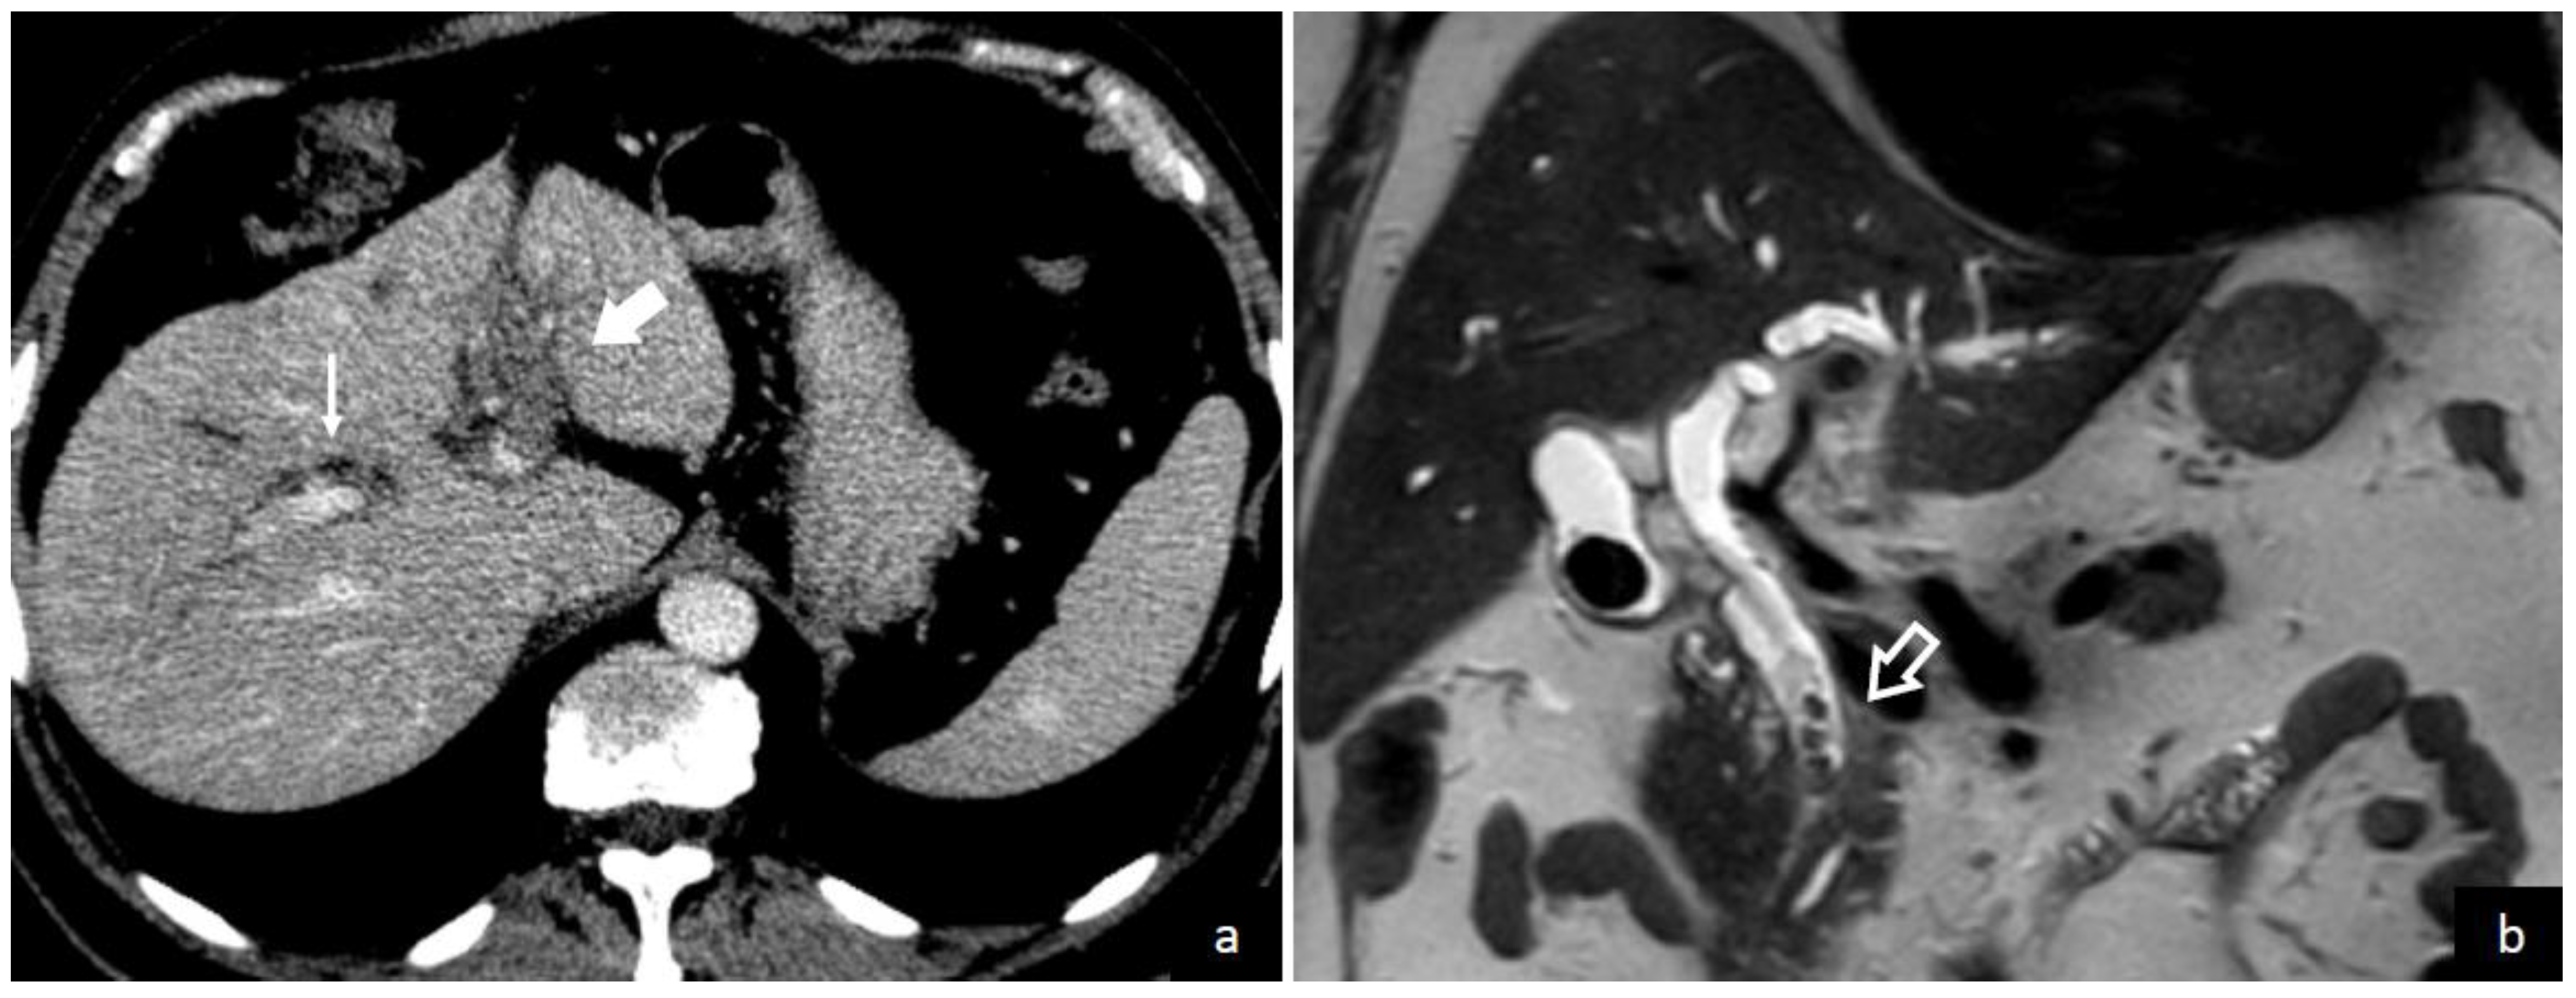

4.2. Imaging Studies